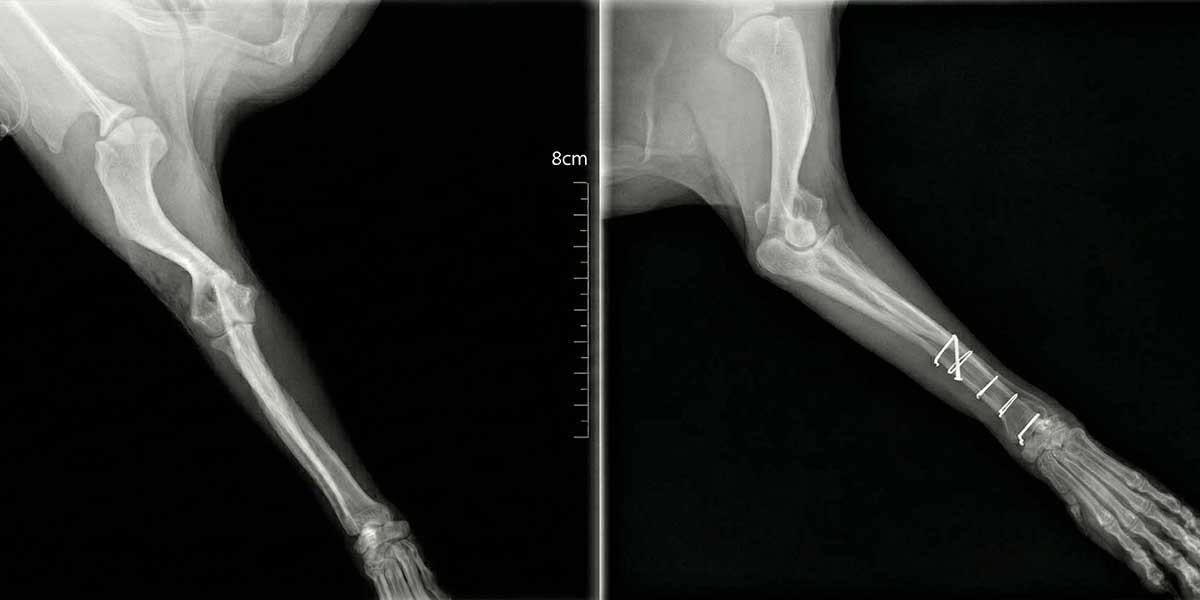

Dijagnoza se postavlja rendgenskim snimkama koje pokazuju lokaciju i tip prijeloma.

Liječenje može biti konzervativno, pomoću gipsa ili udlage, ili kirurško, uključujući pločice, vijke, čavle ili vanjsku fiksaciju.

Kirurško liječenje omogućuje precizno poravnanje kostiju i stabilnost tijekom cijeljenja, što skraćuje vrijeme oporavka.